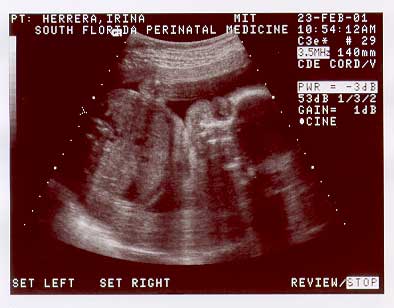

Welcome to the second page of Nicolas' u/s images taken on Feb. 23. 2001, at 25 wks.

BABY-2-25WK-3.jpg (20112 bytes)

Image sequence 6 of 6